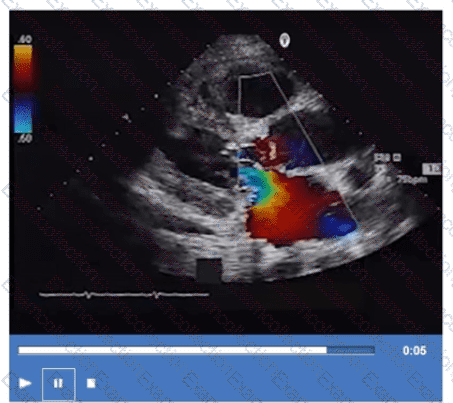

What is the direction of the mitral regurgitant jet in this video clip?